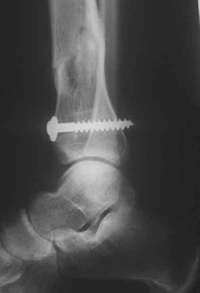

postoperativ (ap)

1 Jahr nach der Operation

Der Patient lief schmerzfrei!